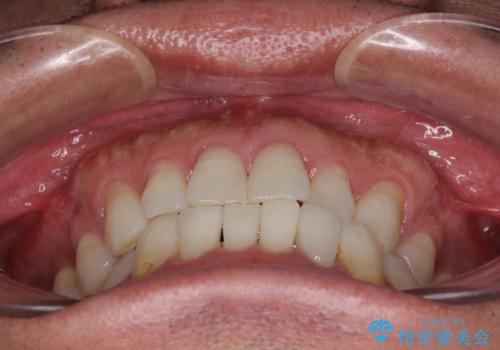

- 治療期間

- 11ヶ月

セラミッククラウンとの干渉はすぐに改善され、歯列も整いましたが、一方で、前歯で食事が噛みにくくなり、1年近い治療期間となりました。